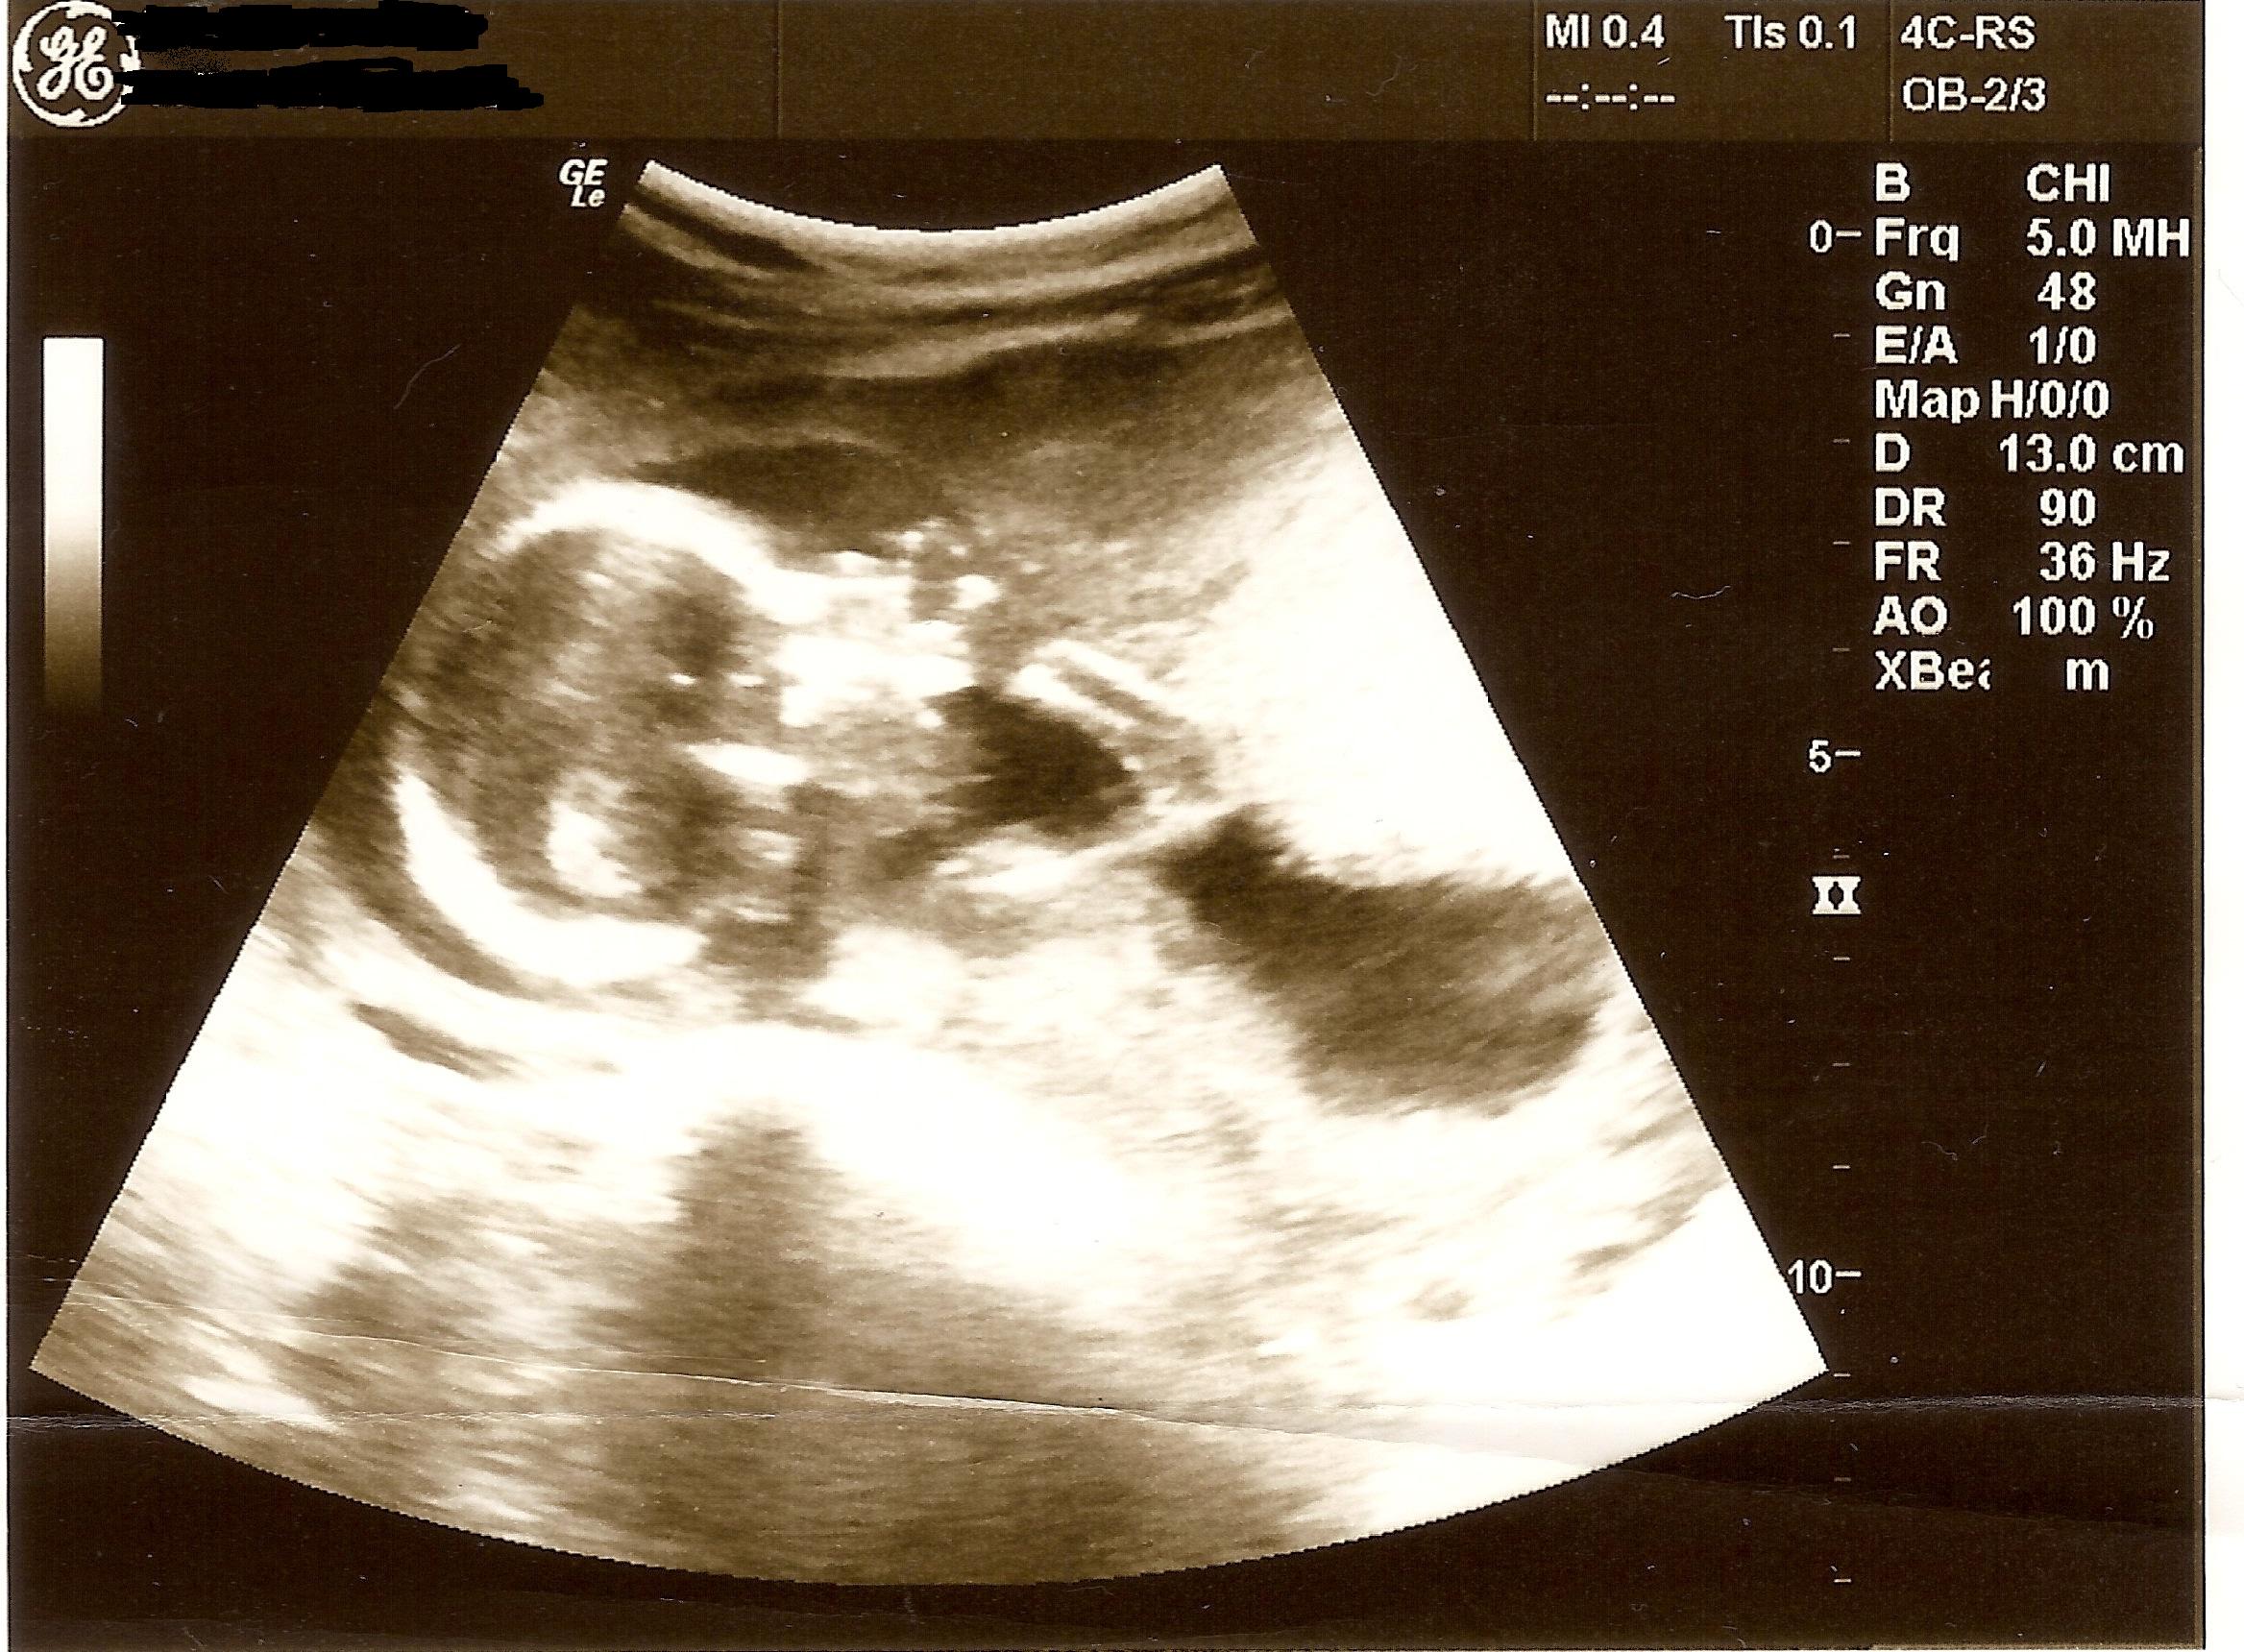

Please help girl or boy skull theory